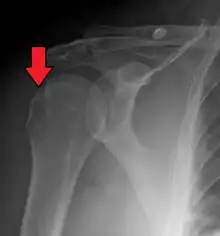

Anterior shoulder dislocation on X-ray with a large Hill–Sachs lesion | |

A Hill–Sachs lesion, or Hill–Sachs fracture, is a cortical depression in the posterolateral head of the humerus. It results from forceful impaction of the humeral head against the anteroinferior glenoid rim when the shoulder is dislocated anteriorly.

Diagnosis can be suspected by history and physical examination which is usually followed by imaging. Because of the mechanism of injury, apprehension of anterior dislocation is common with provocative maneuvers. Hill–Sachs lesions have been classified as "engaging" or "non-engaging", with engaging lesions defined by the ability of the glenoid to sublux into the humeral head defect during abduction and external rotation. Engaging dislocations have a higher risk of recurrent anterior dislocation, and their presence can help guide surgical management.[2] Imaging diagnosis conventionally begins with plain film radiography. Generally, anteroposterior (AP) radiographs of the shoulder with the arm in internal rotation offer the best yield while axillary views and AP radiographs with external rotation tend to obscure the defect. However, pain and tenderness in the injured joint make appropriate positioning difficult and in a recent study of plain film x-ray for Hill–Sachs lesions, the sensitivity was only about 20%. i.e. the finding was not visible on plain film x-ray about 80% of the time.[3]